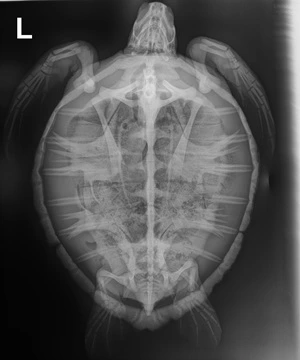

8.6 lb non-FP juvenile green

Moderate plastron abrasions and bruising, wounds on all 4 flippers, abrasions on edge of both left and right marginal scutes, moderate abrasions to carapace.